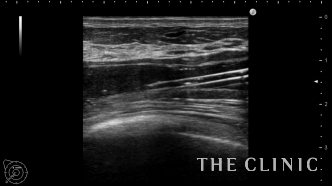

アクアフィリングは生理食塩水で溶解されるとのことで、エコー下に生理食塩水を注入しました。

なかなか溶解できず、ヒアルロニダーゼも追加してなんとか溶解除去することができました。